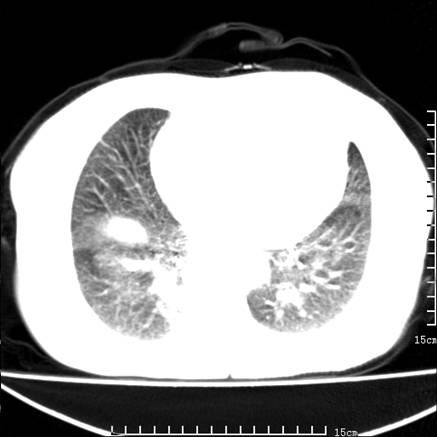

女,王某,58岁,咳嗽三个月余,基层医院二个月前诊为肺结核,用抗结核药二个月无明显疗效。

心包积液致肺瘀血.右侧周围型肺癌伴肺内转移,中间裂积液,叶间胸膜肥厚.右上肺大泡,右侧胸膜肥厚.

双肺继发型tb,心功能不全并肺淤血、心包、双侧叶间裂积液,肺大泡,右下胸膜肥厚钙化。

支持  双肺继发型tb,心功能不全并肺淤血、心包、双侧叶间裂积液,肺大泡,右下胸膜肥厚钙化。